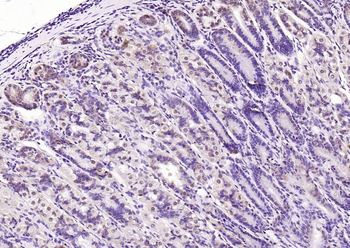

100 μl, 50 μl, 25 μl - Rad51 Recombinant Rabbit Monoclonal Antibody [orb608069]Featured

IF, IHC-Fr, IHC-P, WB

Human, Mouse, Rat

Mouse, Rat

Rabbit

Recombinant

Unconjugated

50 μl, 100 μl - KLF4 Recombinant Rabbit Monoclonal Antibody [orb608075]Featured